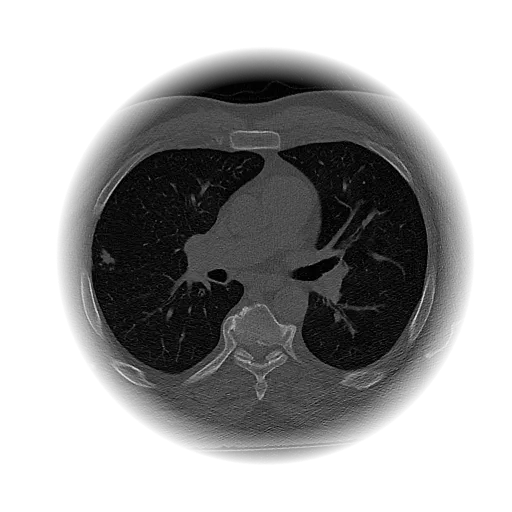

Lung Nodule Detection and Tracing Across Scans

Obvios.ai utilizes cutting-edge artificial intelligence to meticulously detect and track lung nodules, facilitating swift and precise diagnostics, thereby ensuring superior care and timely intervention for patients.